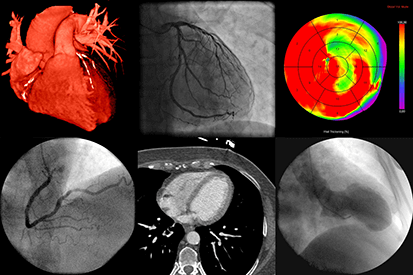

Advanced Heart and Vascular Institute focuses on minimally invasive surgical and medical treatment of heart, vascular, and venous diseases. We specialize in complex invasive heart and vascular procedures, including coronary artery stenting, lower extremity arterial stenting, and TAVR (aortic valve replacement) without open heart surgery. We also specialize in minimally invasive treatment for varicose vein disease.

The specialists at Advanced Heart and Vascular Institute are high-volume cardiac procedural operators. In fact, they are in the top 5% for volume. This means we have a tremendous amount of experience, providing patients with better results and fewer complications. We treat our patients like family, which makes our treatments and quality of care exceptional.